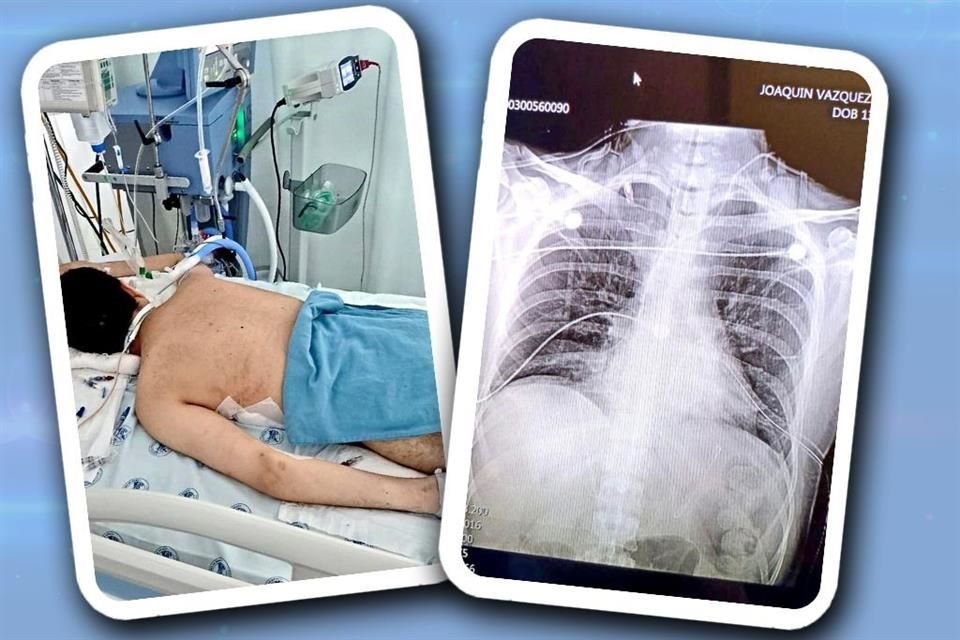

Jordi, un joven de 30 años con esquizofrenia, está hospitalizado en estado grave, a causa del desabasto de psicofármacos, acusan familiares.

Jordi, un joven de 30 años con esquizofrenia, está hospitalizado en estado grave, a causa del desabasto de psicofármacos, acusan familiares. Crédito: Especial.

Jordi, un joven de 30 años con esquizofrenia, está hospitalizado en estado grave, a causa del desabasto de psicofármacos en el sector salud, acusan sus familiares.